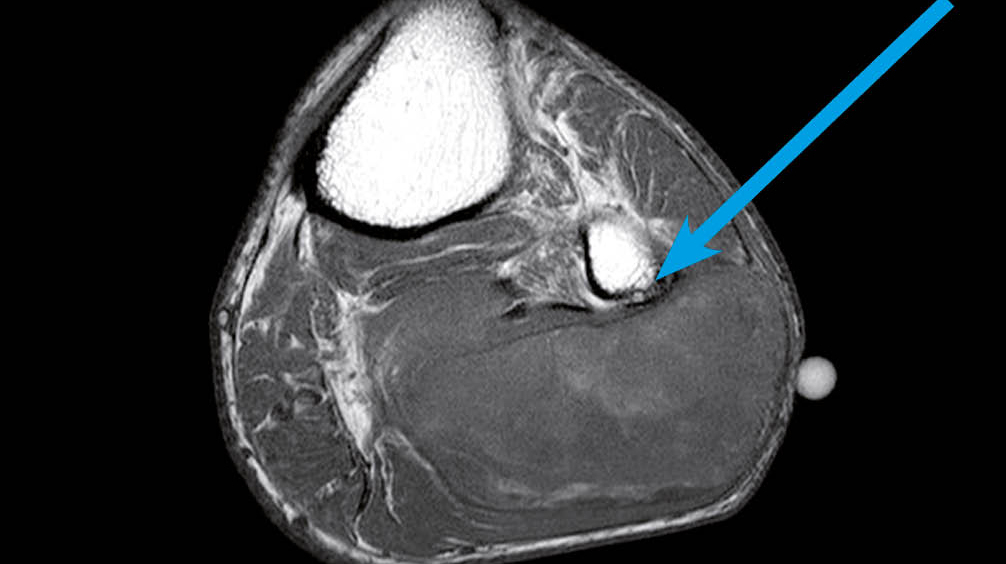

Drei Monate nach Austritt stellte sich der Patient bei seinem Hausarzt vor und beklagte rechtsseitige atemabhängige thorako-abdominale Schmerzen. Das CT Thorax/Abdomen wurde vorgezogen. Dies zeigte, neu zur Voruntersuchung, eine rechtsseitige grosse retroperitoneale Raumforderung mit vorwiegend lipomatösen Anteilen (Abb. 3). Weitere Abklärungen wie auch eine spezifische Therapie hat der Patient abgelehnt. Eine «best supportive care» Therapie mit peroraler Analgesie erfolgte mit Paracetamol und Metamizol bei Bedarf, worunter sich eine gute Schmerzkon­trolle zeigte. Der Allgemeinzustand war noch gut.

Als Risikofaktoren gelten genetische Prädisposition, Radio- oder Chemotherapie, chemische Karzinogene, chronische Irritation und Lymphödem. Das Leitsymptom ist eine schmerzfreie wachsende tumoröse Struktur. Lokale typische Tumorinvasion ist selten. Metastasierung erfolgt vor allem hämatogen und meistens in die Lunge. Als Ausnahme metastasiert das Liposarkom vom myxoiden Typ typisch in das Retroperitoneum, Abdomen, Wirbelsäule und paravertebrale Weichteilgewebe und eher selten in die Lunge.

Zum Staging wird das «Union internationale contre le cancer» (UICC) Klassifikationssystem verwendet. Das Staging muss ein Spiral-CT-Thorax enthalten. Bei myxoidem Liposarkom der Extremitäten muss zusätzlich ein Abdomen-CT durchgeführt werden. Szintigraphie, Ganzkörper MRI und PET Scan sind optional. Lymphknotenmetastasen sind selten.

High risk Patienten haben ein Rezidiv in den ersten 2 - 3 Jahren. Low risk Patienten entwickeln, wenn überhaupt, erst spät ein Rezidiv. Dem endsprechend sollten high risk Patienten in den ersten 2 - 3 Jahren alle 3 - 4 Monate mittels CT/MRI nachkontrolliert werden. Danach sollten weitere Kontrollen im 6-monatigen Intervall erfolgen. Ab dem 5. Jahr sind jährliche Kontrollen indiziert. Low Risk Patienten sollten alle 4 - 6 Monate mittels konventionellem Thoraxröntgen oder Thorax-CT in den ersten 3 - 5 Jahren nachkontrolliert werden und dann weiter jährlich. Im Gegensatz zu den anderen Sarkomen, sollen die Nachkontrollen beim myxoiden Liposarkom zusätzlich ein Abdomen-CT enthalten wegen der atypischen Metastasierung in das Retroperitoneum/Abdomen.